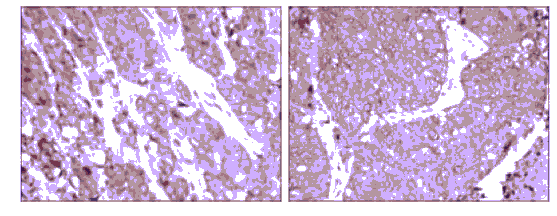

IHC (Immunohiostchemistry)

(Immunohistochemical analysis of paraffin-embedded prostate cancer tissues (left) and lung cancer tissues (right) using HSP90AB1 mouse mAb with DAB staining.)